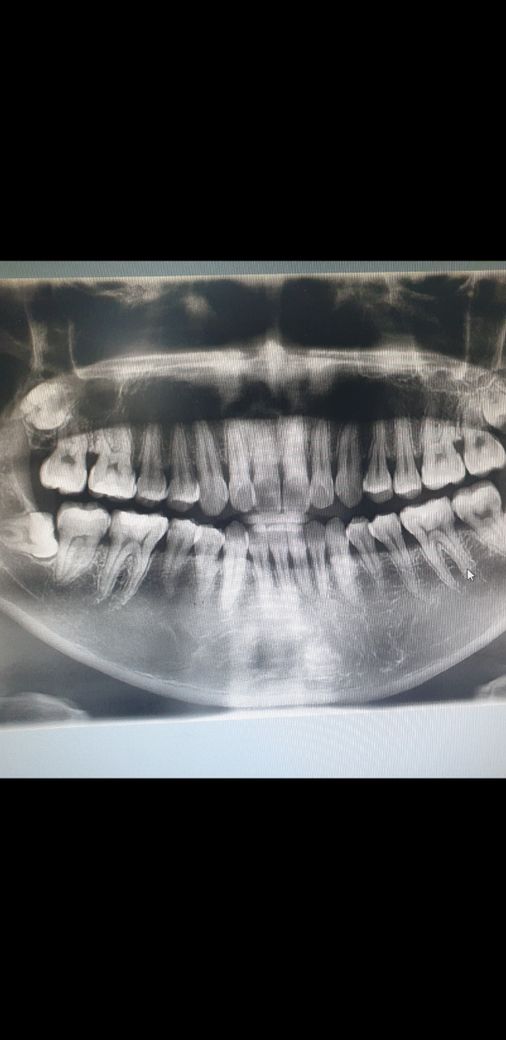

잇몸퇴축 어느정도 진행중인가요? 도와주세요

반년 전에 찍엇는데 의사가 잇몸퇴축 되고있다고한게 기억이나서 질문드립니다 ㅠ이사진으로 퇴축진행되고있는건지 알수있을까요?

잇몸의 퇴축이 보이긴 하지만 퇴축의 진행 정도는 알수는 없고..정기적인 스켈링이 도움이 됩니다.

해당 사진으로는 퇴축이 진행되고 있는지는 알 수 없으며 일정 기간 동안 촬영한 연속적인 사진이 필요합니다. 해당 사진에서는 특별히 진행성이라고 판단되는 부분은 없습니다.

파노라마 사진으로 보았을 때는 경미한 잇몸 퇴축으로 보여지며 관리를 잘 한다면 잇몸 퇴축 정도를 줄일 수 있을 것으로 보입니다.

나이에 따라서 달라질수도 잇을것같습니다. 젊으시다면 나이에 비해서 잇몸이 조금 내려가신거 같지만 연세가 잇으신분이라면 크게 문제가 잇어 보이진 않습니다.

전보다 진행이 되고있는지는 알수없으나 잇몸이 전체적으로 내려간것으로 보입니다. 주기적인 스케일링 및 잇몸치료를 통해 잘관리해주셔야 합니다